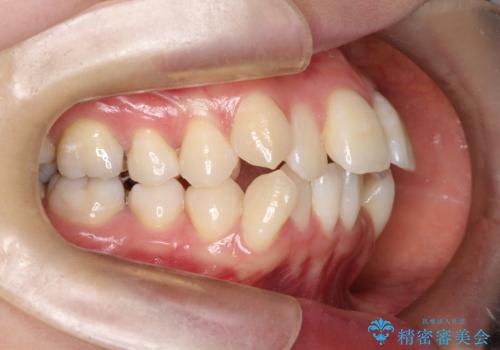

- 出っぱによる口元の閉じにくさを主訴に来院されました。上顎の出っ歯と上下顎叢生も認められたため、上下顎両側4番抜歯を行い、ワイヤー矯正で治療する治療計画を立てました。

上顎にはMI(マイクロインプラント)を埋入して固定源とすることで出っ歯の改善を図りました。

少しスペースクローズに時間がかかりましたが、MIを用いたワイヤー矯正で

主訴である出っ歯と叢生が改善されました。口も閉じやすくなり、スッキリとした口元になりました。